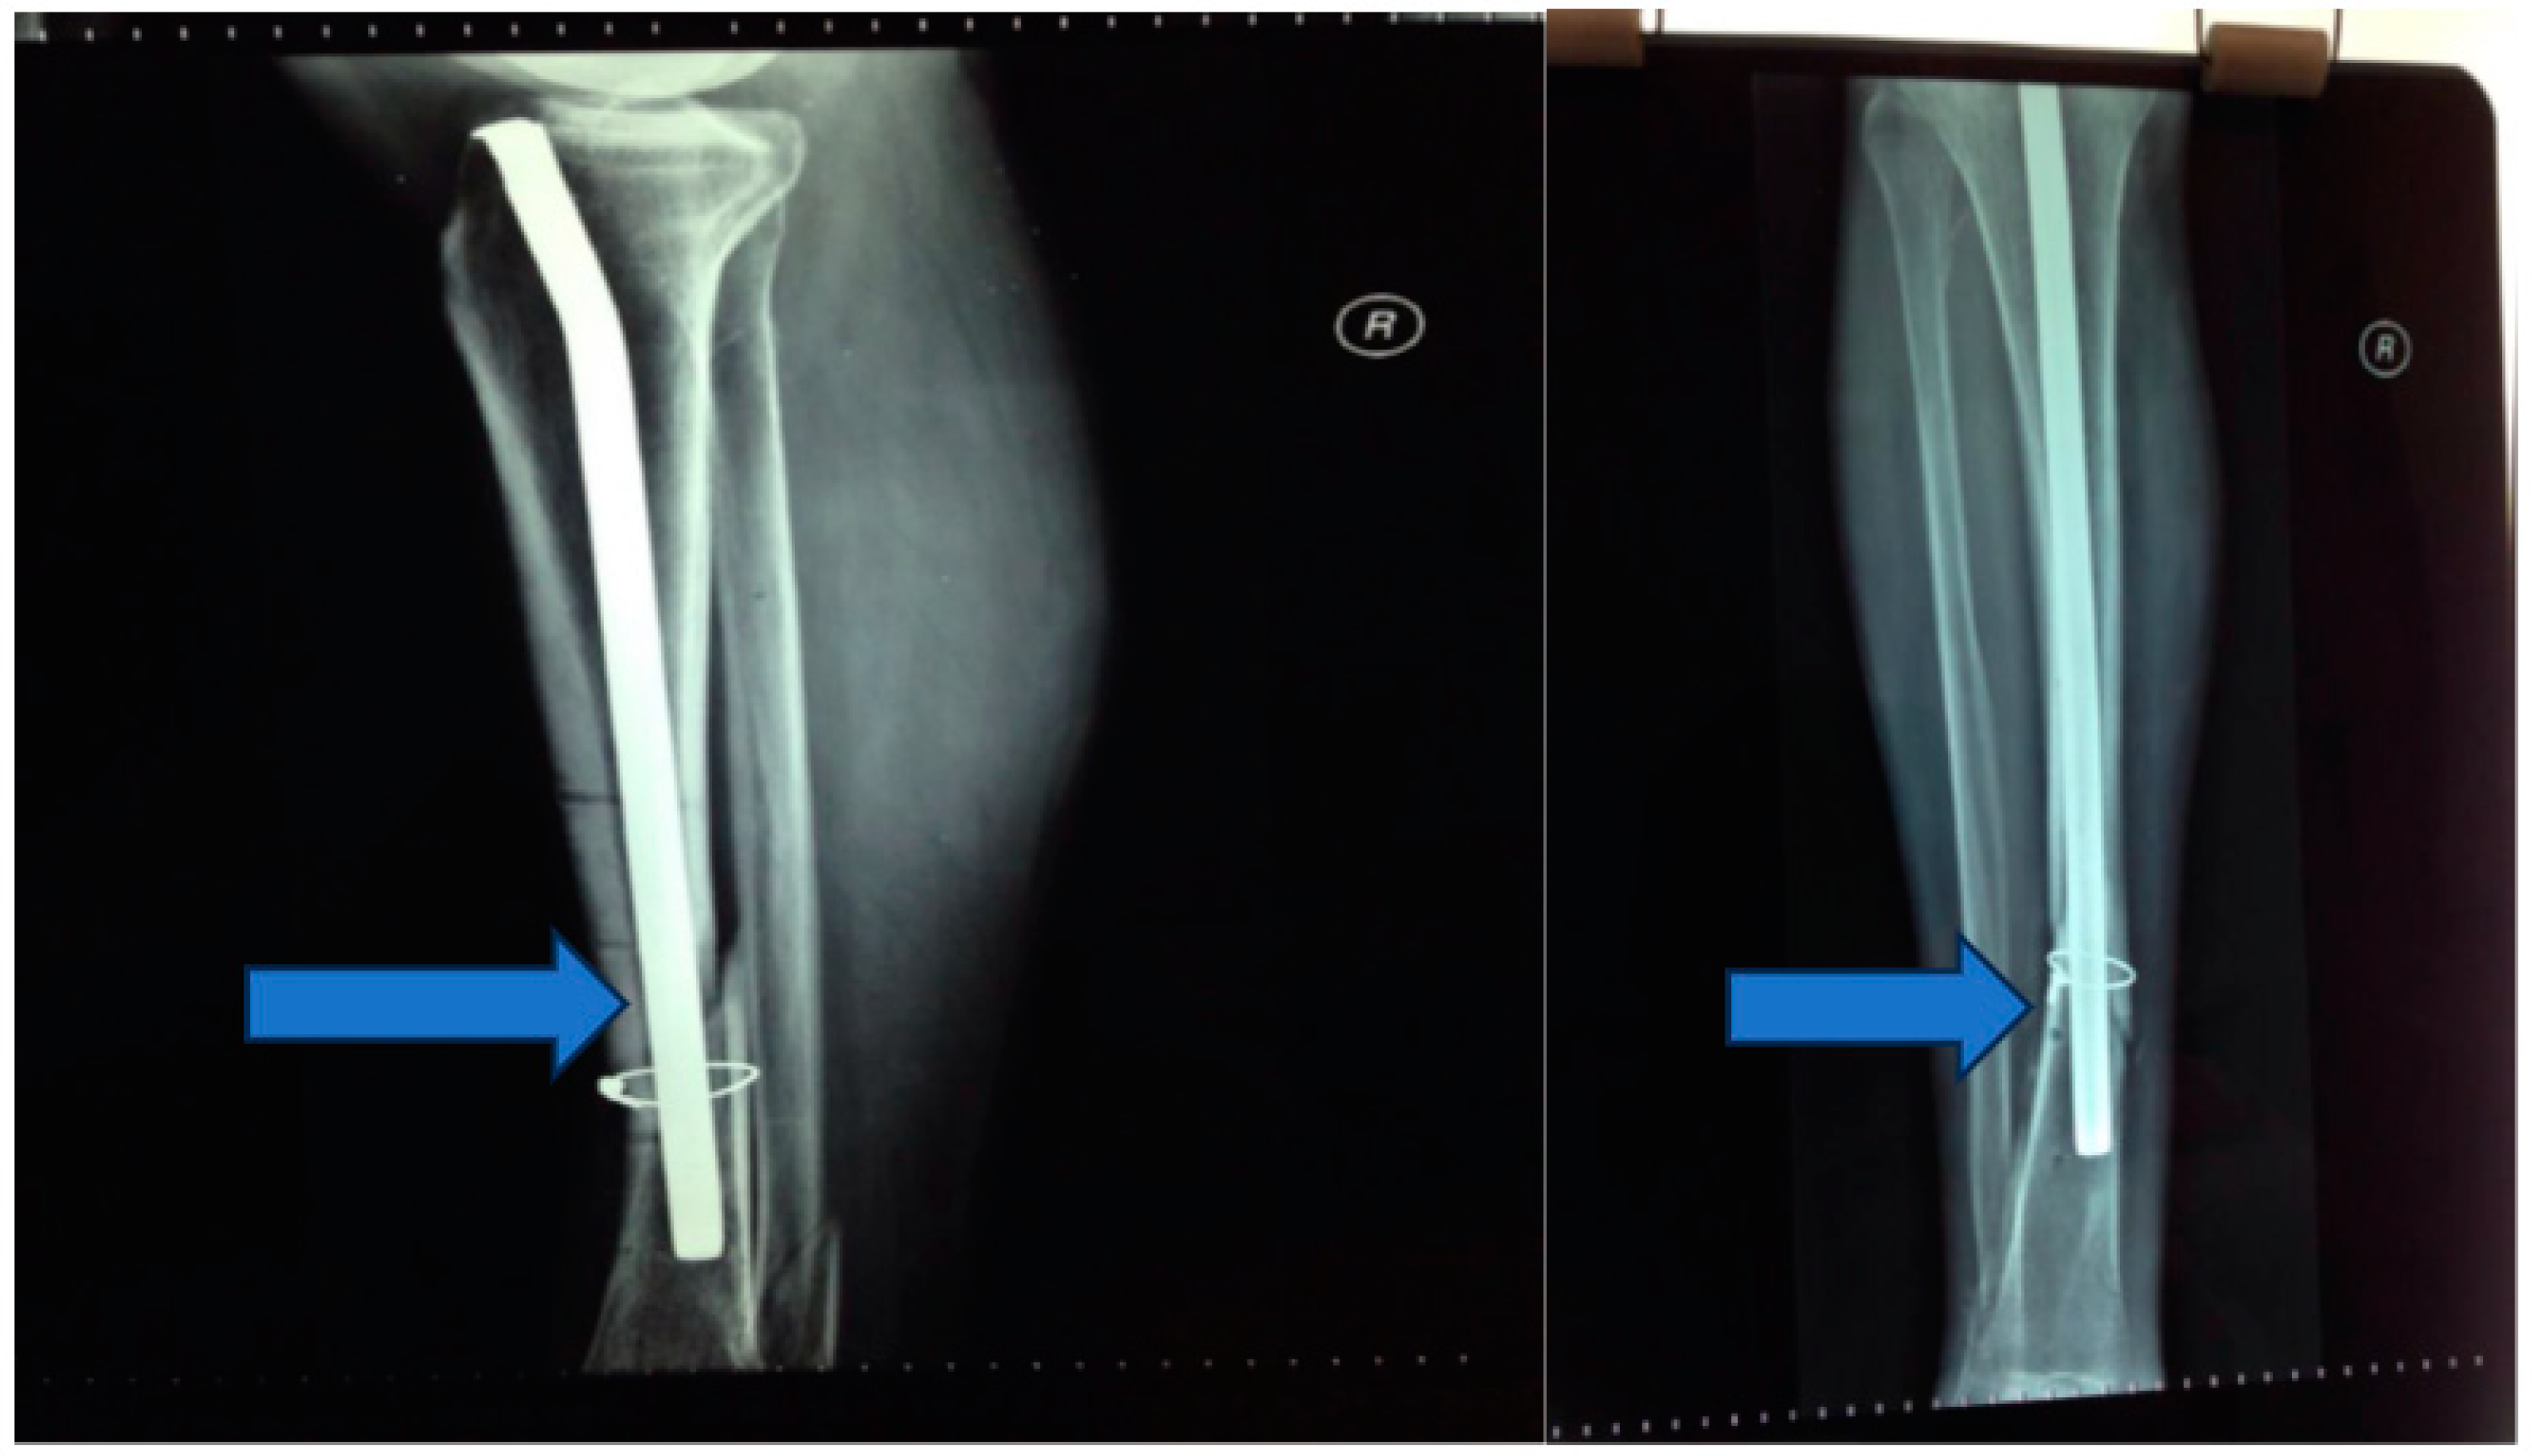

Stage 3: Grafting for osteo-muscular defect (Figure 5).

Objective: To address the osteo-muscular defect and facilitate tissue regeneration.

Methods: This stage involved grafting the osteo-muscular defect using autografts harvested from the rib and serratus anterior muscle. The external fixation device was maintained to provide support during the graft integration period.

Figure 5. Osteo-muscular defect.